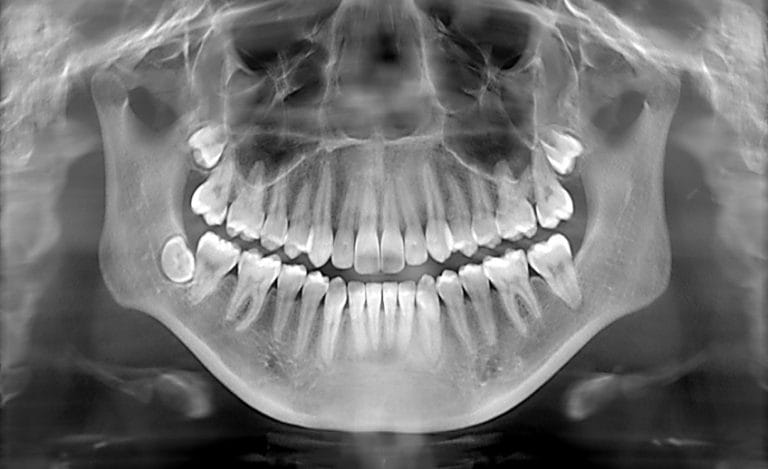

What Dental X-Rays Actually Show

During a dental examination, dentists visually inspect the teeth, gums, and soft tissues. However, certain problems develop in areas that cannot be seen directly.

Dental X-rays help reveal:

• Cavities between teeth

• Infections near tooth roots

• Bone loss around teeth

• Impacted teeth

• Hidden structural damage

Without radiographs, these conditions could progress quietly until discomfort or visible damage appears.